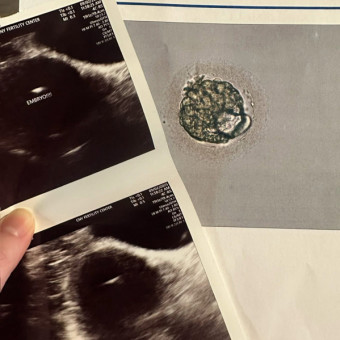

Baby Jaramillo Coming Soon

We are so excited for this little girl to arrive! All of the support from everyone throughout our fertility journey has truly been amazing. Thanks for visiting our registry and your continued support and prayers!

Our journey to baby #2